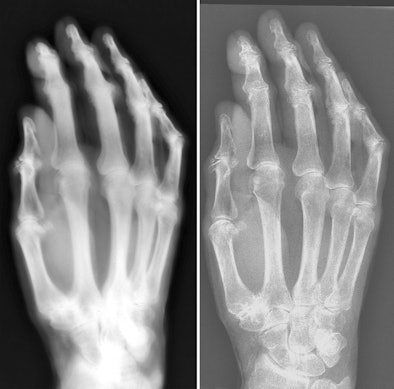

| Images of the hand specimen of an 86-year-old woman obtained with vintage x-ray machine (left) and a modern x-ray system (right). The exposure time with the 1896 system was 21 minutes. |

Although the study revealed the primitive nature of early work in radiology, the researchers said that ultimately they were impressed with the image quality of the device.

"Images of the hand specimen obtained with the antiquated system were severely blurred but were still awe inspiring, considering the simplicity of the system," they concluded.